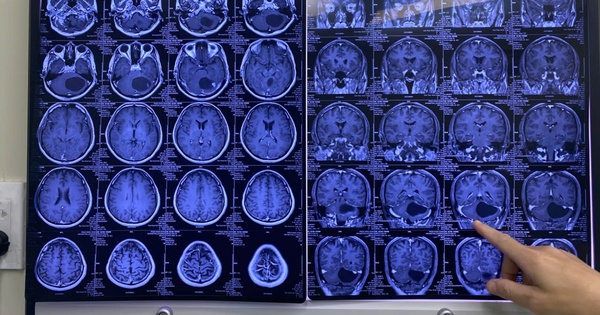

150 phút nghẹt thở với người đàn ông vào bệnh viện trong tình trạng đau đầu dữ dội

(NLĐO)- Với u não, một sơ suất nhỏ có thể gây chảy máu ồ ạt, dẫn đến di chứng liệt toàn thân hoặc tử vong ngay trên bàn mổ.